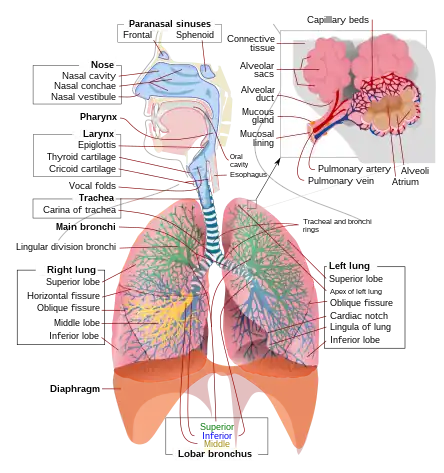

A complete, schematic view of the human respiratory system with their parts and functions. | |

The respiratory system (also respiratory apparatus, ventilatory system) is a biological system consisting of specific organs and structures used for gas exchange in animals and plants. The anatomy and physiology that make this happen varies greatly, depending on the size of the organism, the environment in which it lives and its evolutionary history. In land animals, the respiratory surface is internalized as linings of the lungs.[1] Gas exchange in the lungs occurs in millions of small air sacs; in mammals and reptiles, these are called alveoli, and in birds, they are known as atria. These microscopic air sacs have a very rich blood supply, thus bringing the air into close contact with the blood.[2] These air sacs communicate with the external environment via a system of airways, or hollow tubes, of which the largest is the trachea, which branches in the middle of the chest into the two main bronchi. These enter the lungs where they branch into progressively narrower secondary and tertiary bronchi that branch into numerous smaller tubes, the bronchioles. In birds, the bronchioles are termed parabronchi. It is the bronchioles, or parabronchi that generally open into the microscopic alveoli in mammals and atria in birds. Air has to be pumped from the environment into the alveoli or atria by the process of breathing which involves the muscles of respiration.

In humans and other mammals, the anatomy of a typical respiratory system is the respiratory tract. The tract is divided into an upper and a lower respiratory tract. The upper tract includes the nose, nasal cavities, sinuses, pharynx and the part of the larynx above the vocal folds. The lower tract (Fig. 2.) includes the lower part of the larynx, the trachea, bronchi, bronchioles and the alveoli.

The branching airways of the lower tract are often described as the respiratory tree or tracheobronchial tree (Fig. 2).[4] The intervals between successive branch points along the various branches of "tree" are often referred to as branching "generations", of which there are, in the adult human, about 23. The earlier generations (approximately generations 0–16), consisting of the trachea and the bronchi, as well as the larger bronchioles which simply act as air conduits, bringing air to the respiratory bronchioles, alveolar ducts and alveoli (approximately generations 17–23), where gas exchange takes place.[5][6] Bronchioles are defined as the small airways lacking any cartilaginous support.[4]

The first bronchi to branch from the trachea are the right and left main bronchi. Second, only in diameter to the trachea (1.8 cm), these bronchi (1 -1.4 cm in diameter)[5] enter the lungs at each hilum, where they branch into narrower secondary bronchi known as lobar bronchi, and these branch into narrower tertiary bronchi known as segmental bronchi. Further divisions of the segmental bronchi (1 to 6 mm in diameter)[7] are known as 4th order, 5th order, and 6th order segmental bronchi, or grouped together as subsegmental bronchi.[8][9]